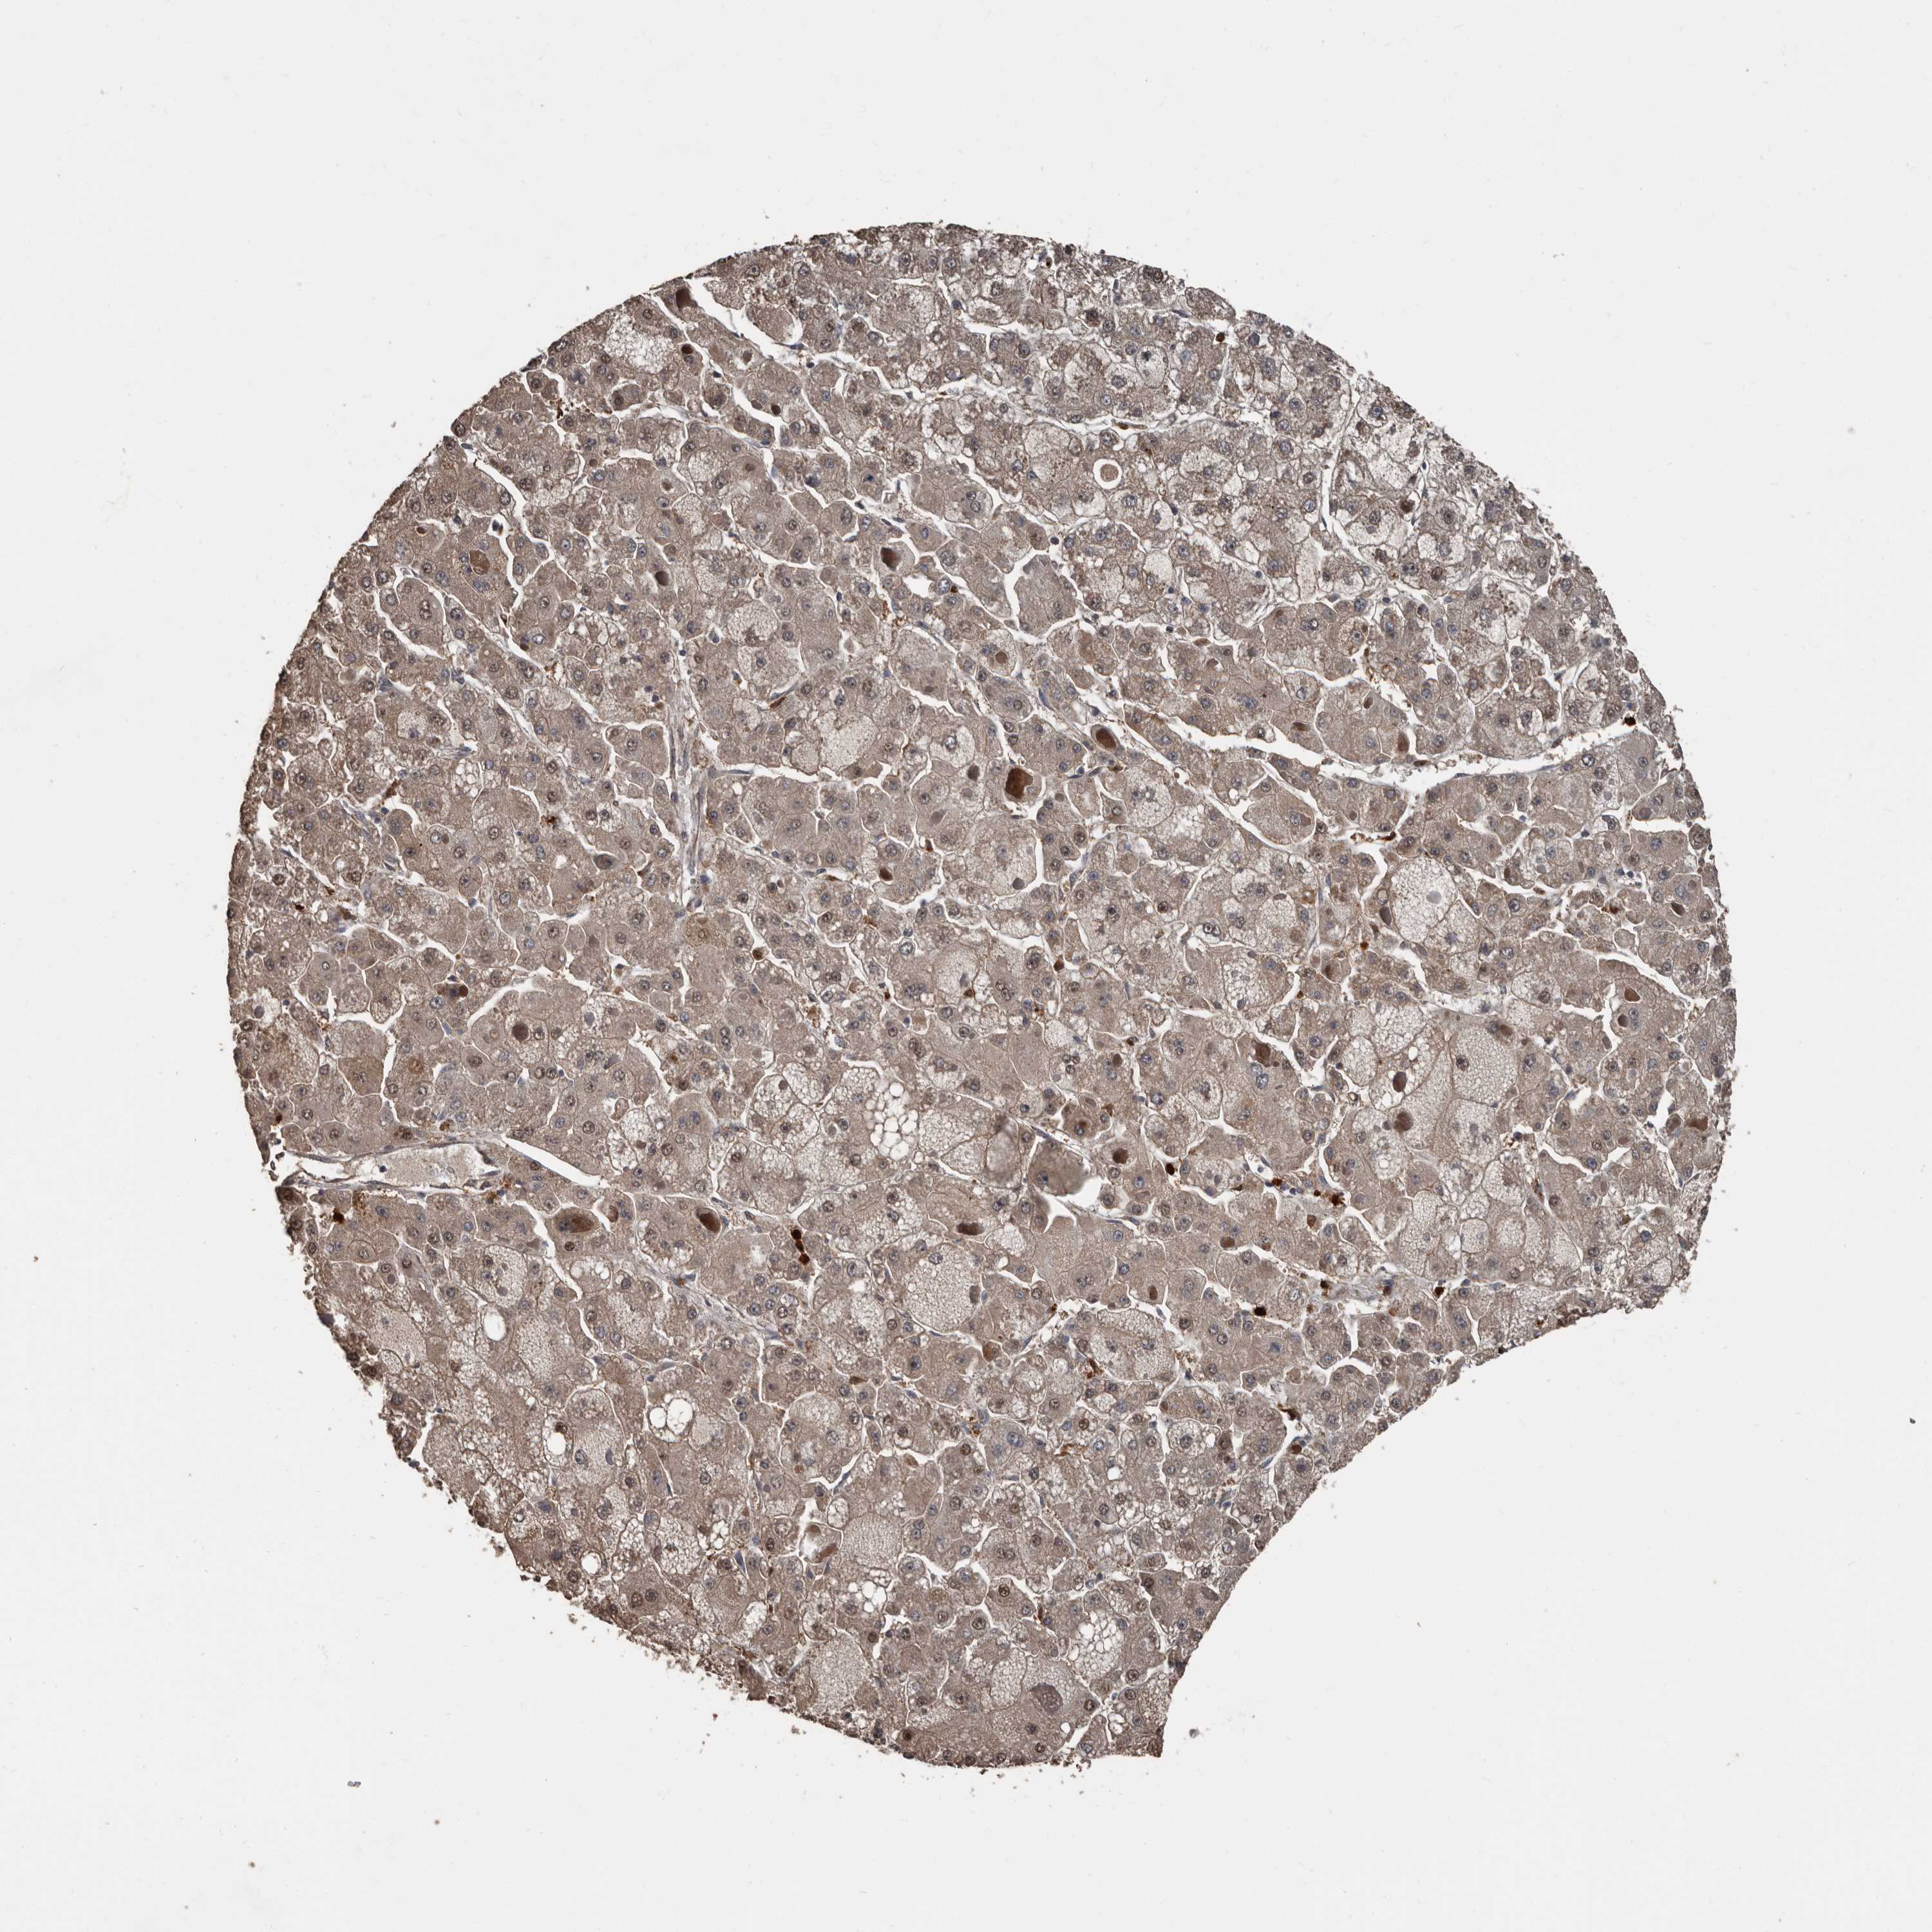

LIVER CANCER - Protein expressioni

A mouse-over function shows sample information and annotation data. Click on an image to view it in a full screen mode. Samples can be filtered based on level of antibody staining by selecting one or several of the following categories: high, medium, low and not detected. The assay and annotation is described here.

Note that samples used for immunohistochemistry by the Human Protein Atlas do not correspond to samples in the TCGA dataset.

Antibody stainingi

Antibody staining in the annotated cell types in the current human tissue is reported as not detected, low, medium, or high, based on conventional immunohistochemistry profiling in selected tissues. This score is based on the combination of the staining intensity and fraction of stained cells.

Each image is clickable and will lead to virtual microscopy that enables deeper exploration of all samples and also displays staining intensity scores, fraction scores and subcellular localization as well as patient and tissue information for each sample.

Antibody HPA026509

Staining

High

Medium

Low

Not detected

Intensity

Strong

Moderate

Weak

Negative

Quantity

>75%

75%-25%

<25%

None

Location

Nuclear

Cytoplasmic/membranous

Cytoplasmic/membranous,nuclear

Cholangiocarcinoma

Carcinoma, Hepatocellular, NOS